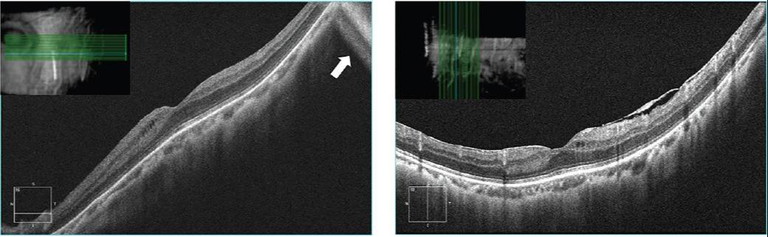

Staphylomas are common in high myopes, and may cause mirror, segmentation and band artefacts (Figures 21 and 22, online*).

After appropriate patient setup and scan alignment, it helps to:

• Allow maximal dilation of the pupil,

• Manually adjust focus on the OCT to match the subjective refraction,

• Reduce the scan length or change the scan direction (vertical, 90°) to enable ‘flattening’ of the scan by running along, rather than across retinal maximum curvature (Figure 13, online* and 23, bottom left),

• In the case of very high myopia that exceeds the device focus range, use contact lenses for OCT, and

• Turn tracking off if necessary.